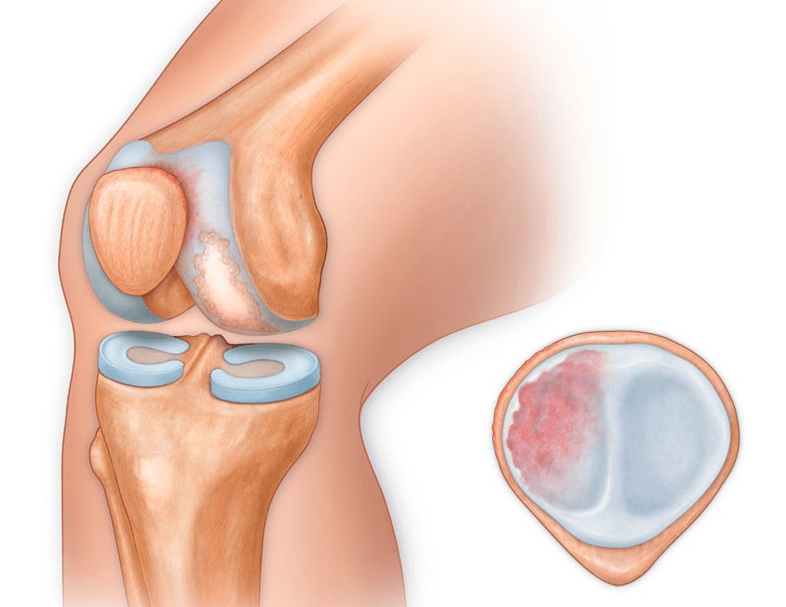

In addition to the inner or outer part of the knee, arthrosis can also affect the surfaces between the patella and the intercondylar groove of the femur.This option is calledpatellofemoral arthrosis.

Its cause is usually subluxation, fracture or lateralization of the patella.

Synovitis of the knee joint is an inflammation of the lining of the inner cavity of the joint.The disease manifests itself in the form of knee swelling, skin redness and limited joint mobility.With the development of arthrosis, synovitis occurs more often, lasts longer and involves a large amount of fluid.